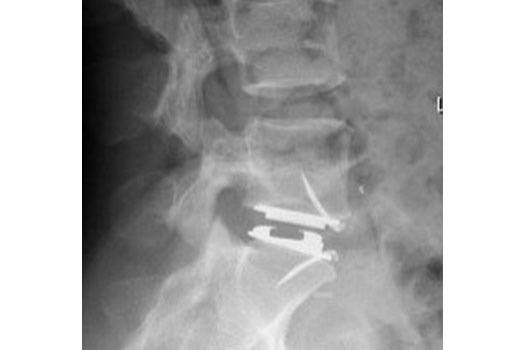

Arthrodèse lombaire antérieure

Cette intervention est proposée en cas de discopathie invalidante, ou en complément d'une arthrodèse postérieure.